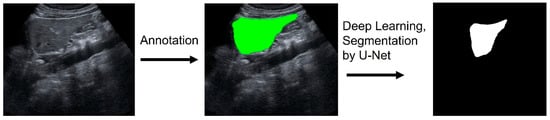

2.5. Image Pre-Processing and Classification of the Liver Surface Roughness via Deep Learning

2.3. Image Pre-Processing and Machine Learning for Liver Segmentation